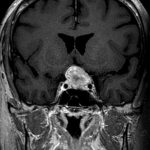

694

'25年11月

90代

頭蓋咽頭腫

頭蓋内腫瘍摘出術

No.’25_96 手術前1

No.’25_96 手術前2